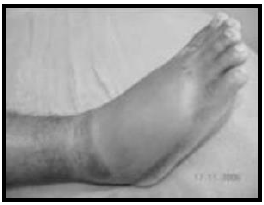

Paciente masculino, de 48 anos, previamente

hígido, refere dor em pé direito após ter sido

picada por um animal desconhecido há 6 horas.

A paciente não conseguiu identificar o animal. Ao

exame físico apresenta bom estado geral,

corado, presença de hiperemia, petéquias e

edema moderado em pé direito. Sistema

cardiovascular, respiratório, neurológico e

abdome sem alterações, frequência cardíaca de

90 bpm e pressão arterial de 110 x 80 mmHg.

Imagem do pé encontra-se na figura abaixo.

Sobre a hipótese diagnóstica mais provável, assinale a alternativa correta.